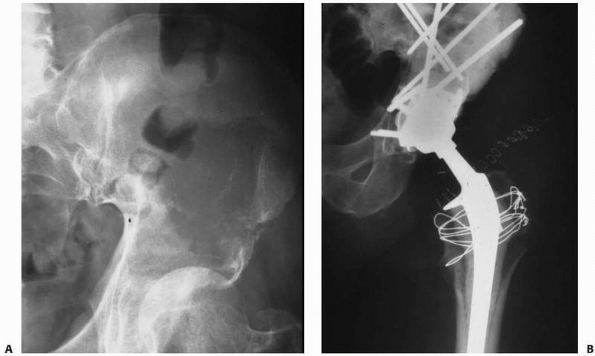

FIGURE 20-7 A.

Anteroposterior radiograph of the left hip in a 61-year-old woman with metastatic breast cancer. Note the femoral head protrusion into the pelvis through a pathologic acetabular fracture. It is important to try and identify metastatic lesions before they fracture so that prophylactic fixation can be performed. Note the extensive bone loss in the superior dome and medial wall. This would be categorized as a Class II lesion. B. Postoperative radiograph after acetabular reconstruction with an antiprotrusion cage, multiple screws, and PMMA. |